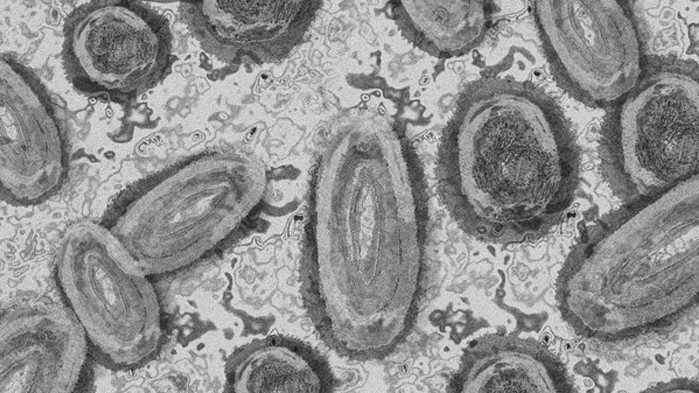

Маймунската шарка плъзна и в Китай

Китайският град Чунцин съобщи за един случай на заразяване с вируса на маймунската едра шарка. Това е първият известен случай на заразяване с маймунска едра шарка в континентален Китай на фона на глобалната епидемия от вируса, информира bg-voice.

Маймунската шарка причинява предимно кожни обриви и треска. Може да бъде фатално, но при сегашното огнище в Европа и САЩ случаите обикновено са леки и смъртността е доста под един смъртен случай на 1000 потвърдени случая.

Въпреки че маймунската шарка е ендемична в Централна и Западна Африка от десетилетия, тази година е първата година, в която вирусът, който я причинява, се разпространява в световен мащаб.